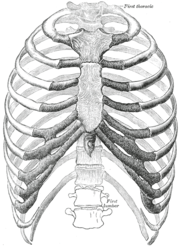

![]() القفص الصدري البشري. (Source: Gray's Anatomy of the Human Body, 20th ed. 1918.) | |

القفص الصدري جزء من الهيكل العظمي البشري يتكون الهيكل العظمى عند الانسان من الهيكل المحورى والهيكل الطرفى حيث نجد ان الهيكل المحورى يتكون من العمود الفقرى والقفص الصدرى والجمجمة . القفص الصدرى عند الانسان يتكون:

- 12 زوج من الضلوع التى ترتبط الجزء الخلفى منها بالعمود الفقرى.

- العشرة ازواج الاولى من الضلوع تتصل من الامام بعظمة القص

- الزوجان السفليان سائبان يسميان بالضلوع العائمة

وظائفه

- حماية القلب والرئتين و المساعدة في عمليتي الشهيق والزفير.